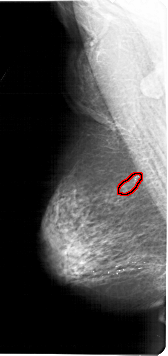

A_1123_1.LEFT_CC

LEFT_CC LINES 6256 PIXELS_PER_LINE 3076 BITS_PER_PIXEL 12 RESOLUTION 43.5 OVERLAY

FILE: A_1123_1.LEFT_CC.OVERLAY

TOTAL_ABNORMALITIES 1

ABNORMALITY 1

LESION_TYPE CALCIFICATION TYPE PLEOMORPHIC DISTRIBUTION SEGMENTAL

LESION_TYPE MASS SHAPE LOBULATED MARGINS ILL_DEFINED

ASSESSMENT 4

SUBTLETY 4

PATHOLOGY BENIGN

TOTAL_OUTLINES 1

BOUNDARY